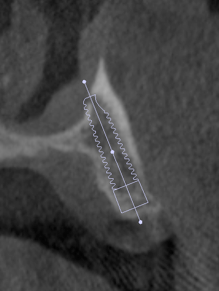

術前のCT右側

術前のCT左側